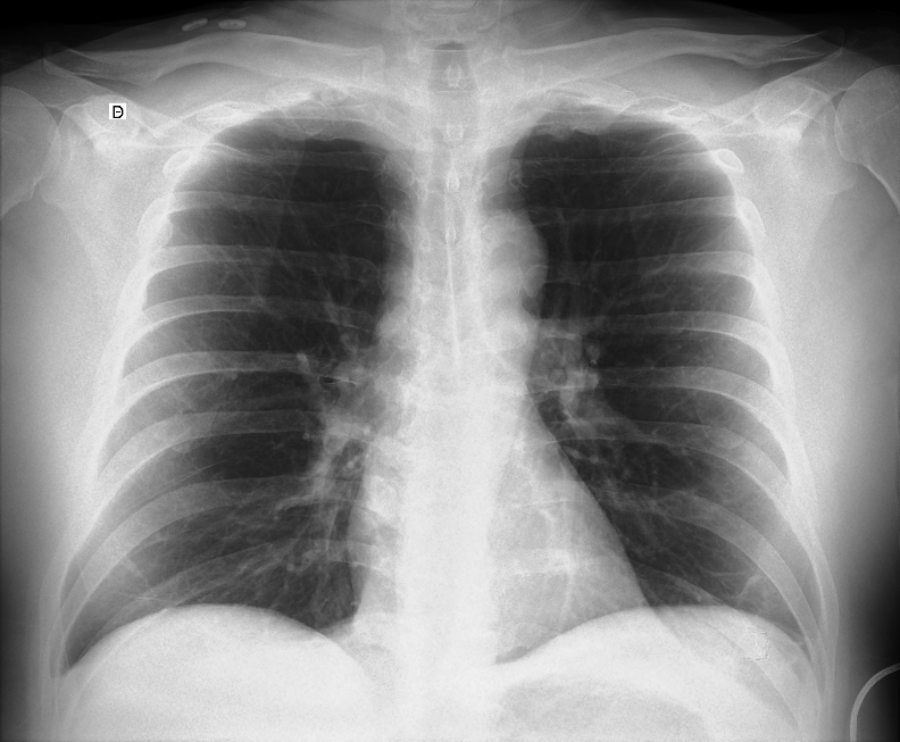

1. Empezá por la base: la radiografía (Rx)

La radiografía suele ser el primer contacto del médico no especialista con la imagen. En el post vas a ver lo esencial: cómo se forma la imagen, qué degrada la calidad y por qué aparecen errores típicos.